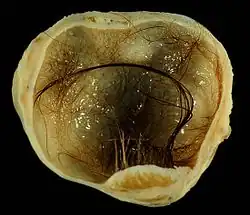

Najczęściej spotykaną odmianą potworniaka dojrzałego jest torbiel skórzasta (łac. cystis dermoidalis), która powstaje wyłącznie ze struktur ektodermalnych (głównie naskórka i jego przydatków). Torbiel skórzasta zawiera w pełni ukształtowane włosy, gruczoły łojowe wydzielające łój naskórkowy, gruczoły potowe, a niekiedy także zdeformowane zęby. Zalecenia klasyfikacyjne nakazują uznawać ją za odrębny typ guza, ale jest to de facto potworniak dojrzały z jednego listka zarodkowego.